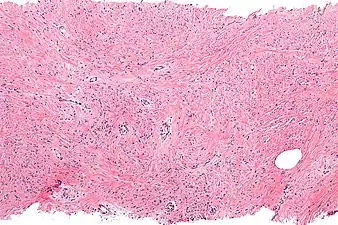

| Micrograph of mammary myofibroblastoma. H&E stain. | |

Intermed. mag. Mammary myofibroblastoma -

Medical imaging may suggest but cannot prove that a tumor is MFB. Mammography, computed tomography scans, and magnetic resonance imaging of mammary[1][12] and extramammary[1][13] MFB typically show well-defined and well-circumscribed tumors which in almost all cases have no calcifications; these results suggest that the tumor is not malignant but do not indicate which type it might be. The diagnosis of MFB depends on the microscopic histopathology (i.e. appearances after proper tissue preparation and staining) of its pre-surgery biopsied issues. As shown in the upper image and the two images in the Additional images section seen below, both mammary and extramammary MFB tissues contain spindle cells, variable numbers of adipocytes (i.e. fat cells) and broad sheets or, less often, thick bundles of collagen fibers.[5] About 4% of cases have an epithelial tumor cell-like morphology,[5] i.e. the tissues are composed predominantly of epithelioid cells variably mixed with a minority (10% to 40%) of round, polygonal, and spindle-shaped cells.[19] Unlike malignant tumors, MFB tumors do not have: a) atypical cells except in the rare cases which contain small clumps of multinucleated cells; b) rapidly proliferating cells as defined by measuring the proliferative index (i.e. fraction of cells undergoing mitosis); or c) areas of necrosis (i.e. areas of dead or dying cells).[16] Microscopy of tumors in the spindle cell lipoma tentative variant of MFB show a mixture of mature fat cells, ropey collagen, and spindle cells in a myxoid (i.e. background connective tissue that stains blue or purple rather than the red of normal connective tissue) matrix.[18] The blood vessels in these tumors often appear hyalinized.[16] Tumor tissues in the tentative cellular angiofibroma variant of MFB contain spindle cells in all cases, fat cells in ~50& of cases, mast cells, peri-vascular infiltrates of lymphocytes, pleomorphic cells in some cases, and cells with some features of the malignant sarcoma cells in sarcoma tumors in rare cases. (The presence of these sarcoma-like cells does not seem to impact the prognosis of this variant.) All of these cells are in edematous-to-fibrous stromatous tissue.[16]